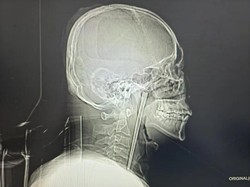

Ngeri! Sumpit Logam 12 Cm Tersangkut di Tenggorokan Pria Selama 8 Tahun

Pria ini hidup dengan sumpit logam yang tersangkut di tenggorokannya selama delapan tahun karena takut menjalani operasi. Begini kisahnya!